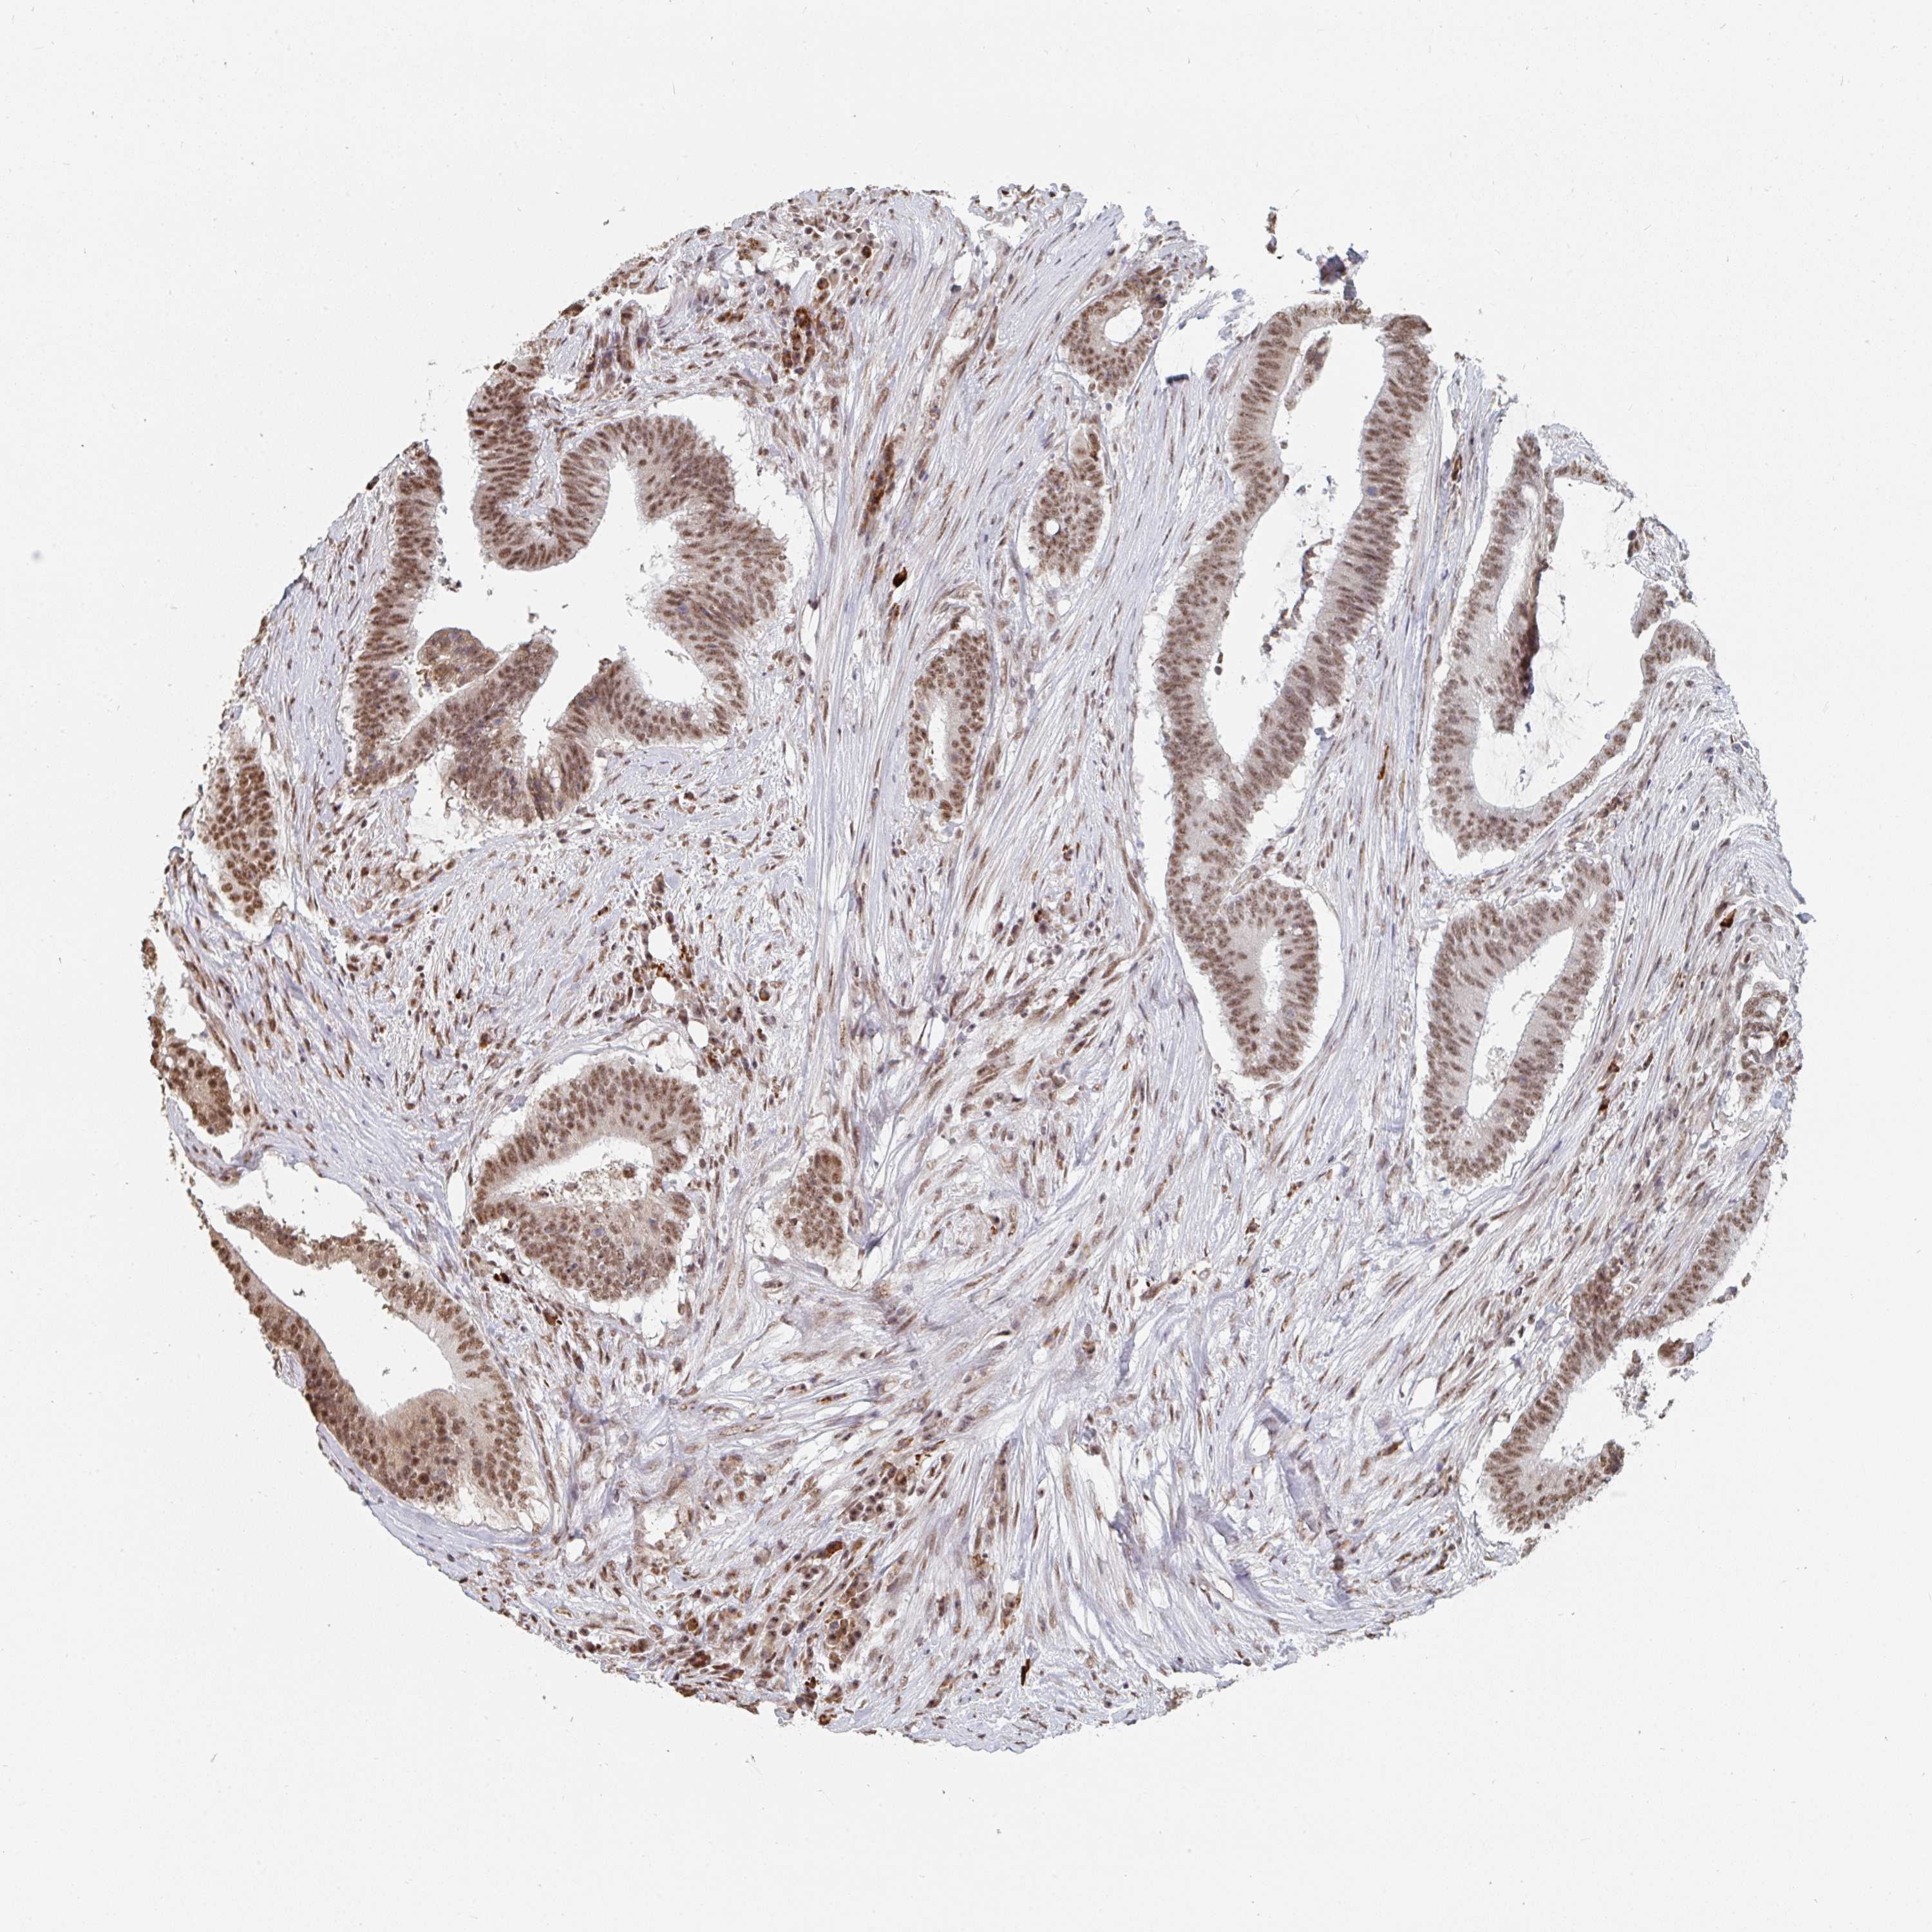

CANCER COLORECTAL CANCER Show tissue menu

Colorectal cancer

Human cancer

Colon adenocarcinoma